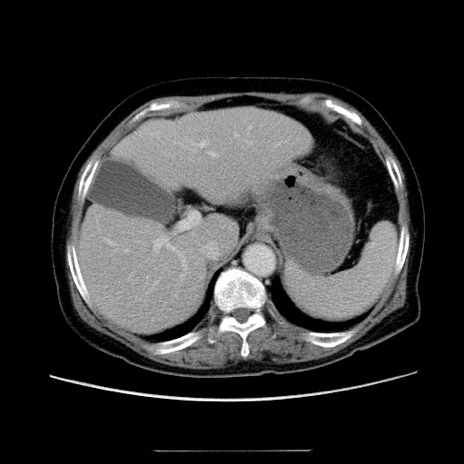

冠状断像

【症例】70歳代女性

【主訴】お腹が張る

【現病歴】1週間くらい前から腹部膨満の自覚あり。昨日夜から増悪したため、本日救急外来受診。

【身体所見】意識清明、BT 36.5℃、BP 165/106mmHg、HR 80bpm、SpO2 98%、腹部:膨満、軟、自発痛・圧痛なし、触診にて不快感あり、腸蠕動音:減弱

【データ】WBC 12600、CRP 1.04